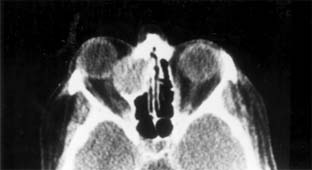

Figure 13-5

Figure 13-5: CT scan of ethmoid sinus mucocele.